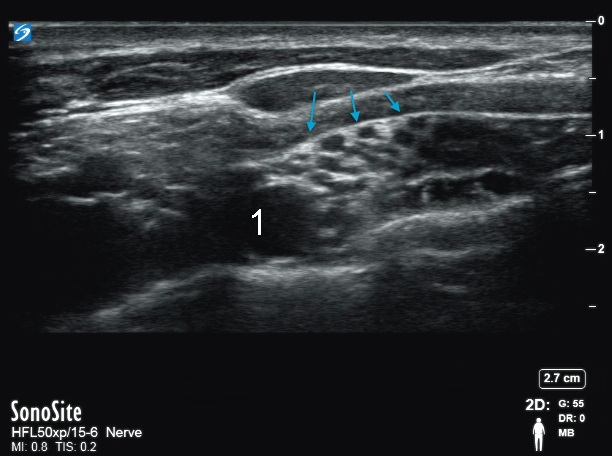

Image : Faisceau nerveux supraclaviculaire

Flèches bleues : Faisceau nerveux

1. Artère supraclaviculaire